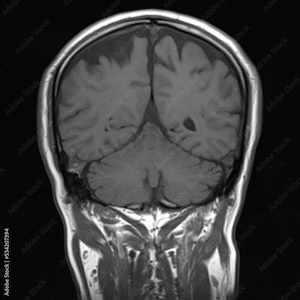

I can speak authoritatively from a patient’s perspective on MRIs, because I’ve had two of them in the past year. The first was for a knee problem, and the second was that the doctors wanted to rule out that I was having a stroke after a blood vessel in my eye popped.

The second thing is that you know what’s being scanned. For my knee, they braced it with a couple of padded clamps to hold it in place. For my brain scan, they fitted a plastic helmet around my head to limit movement. Only an idiot would fail to recognize what the instrument was for.

Thirdly, afterwards the doctors tell you what they found. In one case, they found I had a torn meniscus; in the other, no evidence that I’d had a stroke (that must be what getting a “perfect” MRI means). They both discussed it with me in person and sent me an after-examination document that spelled it all out. They also noted some deterioration of the cervical vertebrae, but my knees, other than the meniscus, were flawless.

I had a cranial MRI done in 2018 after suffering an optical migraine. I’d never had an optical migraine before and thought I was having a stroke (look it up, they’re very weird). My wife rushed me to the ER, where they checked me out and ran a CT scan. Nothing unusual. A week later I had the cranial MRI, and, once again, nothing out of the ordinary was seen — no tumor, blockages, or circulatory pressure on nerves. My point here being, I knew full well what the MRI was for and where on my body it was being conducted. Maybe the better point is that I remembered what the neurologist told me. I believe that’s Trump’s problem, he doesn’t remember. Perhaps it’s high time for him to have a cranial MRI, too.